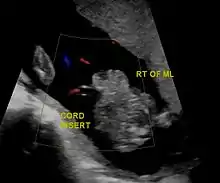

Gastrochisis in ultrasound: defect is right to midline

During the fourth week of human embryonic development, the lateral body wall folds of the embryo meet at the midline and fuse together to form the anterior body wall.[9] However, in gastroschisis and other anterior body wall defects, this fails to occur by either one or both of the lateral body wall folds not moving properly to meet with the other and fusing together.[10] This incomplete fusion results in a defect that allows abdominal organs to protrude through the abdominal wall, and the intestines typically herniate through the rectus abdominis muscle, lying to the right of the umbilicus. The forces responsible for the movement of the lateral body wall folds are poorly understood, and a better understanding of these forces would help to explain why gastroschisis occurs mostly to the right of the umbilicus, while other ventral body wall defects occur in the midline.[9]